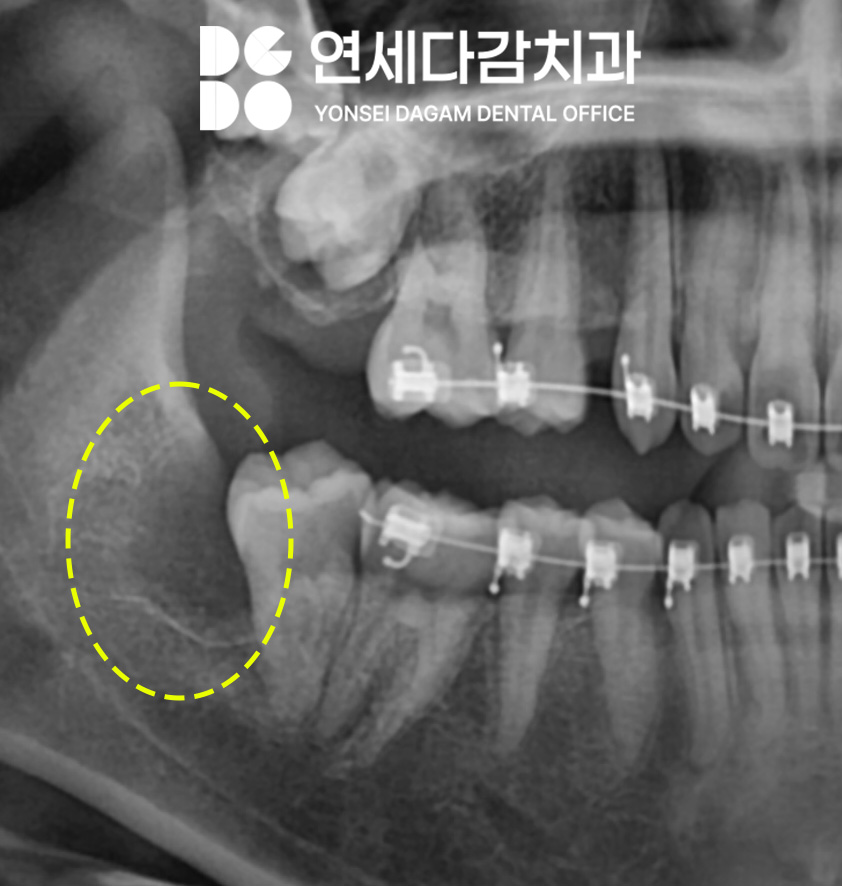

현재 위턱에 표시된 부위가

정상적으로 맹출 되고 있지 않은 상태로,

현재는 정출 유도 장치를 이용하여

경과를 관찰 중입니다.

정출시키는 과정에서 옆에 있는

사랑니가 물리적으로

방해된다고 판단되면,

필요시 추가 조치를 시행할

예정입니다.